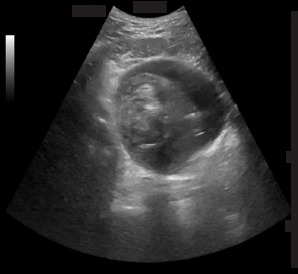

Abstract Image